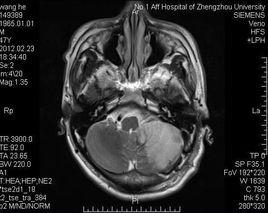

小腦梗塞臨床上一般將小腦梗塞分為三種類型:良性型、假腫瘤型和昏迷型,無論哪一型小腦梗塞發病時都會有頭暈、步態不穩、噁心嘔吐等臨床表型,但後兩種除了小腦症候群外還可以合併偏癱甚至出現昏迷,臨床治療一般給予降纖、抗凝、抗血小板聚集、活血化瘀芳香開竅中藥及脫水降顱壓等藥物治療。